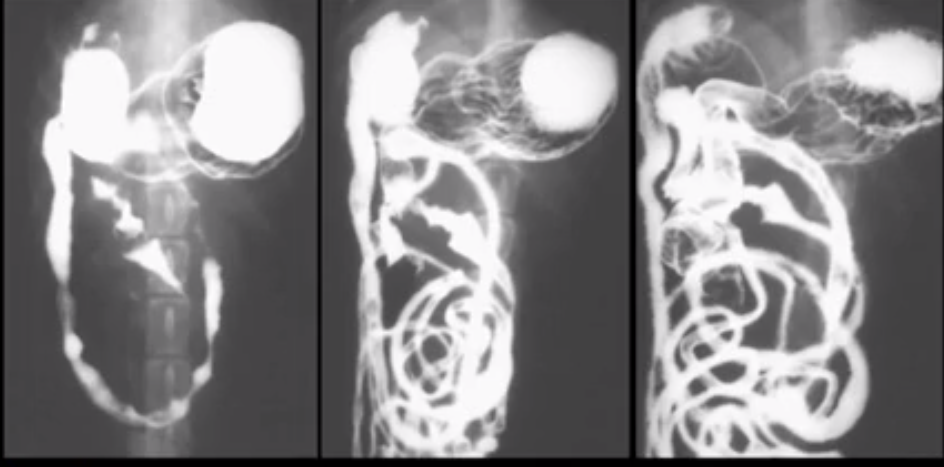

What does this image show?

Duodenal mucosal changes due to pancreatitis

Does this kitten have a complete obstruction? Images taken immediately and 20 mins later.

20 mins later contrast can be seen in rectum so not an obstruction

Corrugated intestine shows hypermotility. Kidney can be seen below.

Descending duodenum. Whiter (hyperechoic or more echogenic) line = R limb of pancreas